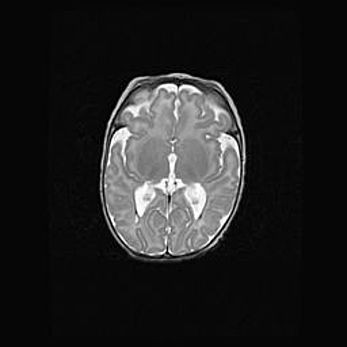

Мальформация Денди-Уокера. Киста задней черепной ямки.

Агенезия мозолистого тела.

Возраст: 2,5 месяца

Вес: 2420 г

Пол: женский

Окружность головы: 37 см

Срок гестации: 32 недели

Мальформация Денди—Уокера — редкий вид патологии ЦНС, представляющий собой врожденный порок развития каудального отдела ствола и червя мозжечка, ведущий к неполному раскрытию срединной (Мажанди) и латеральных (Лушка) апертур IV желудочка мозга. Для этогно синдрома характерна триада симптомов: гипотрофия червя мозжечка и/или полушарий мозжечка, кисты задней черепной ямки, гидроцефалия различной степени. В 70% случаев порок сочетается и с другими аномалиями головного мозга, в частности с агенезией мозолистого тела.